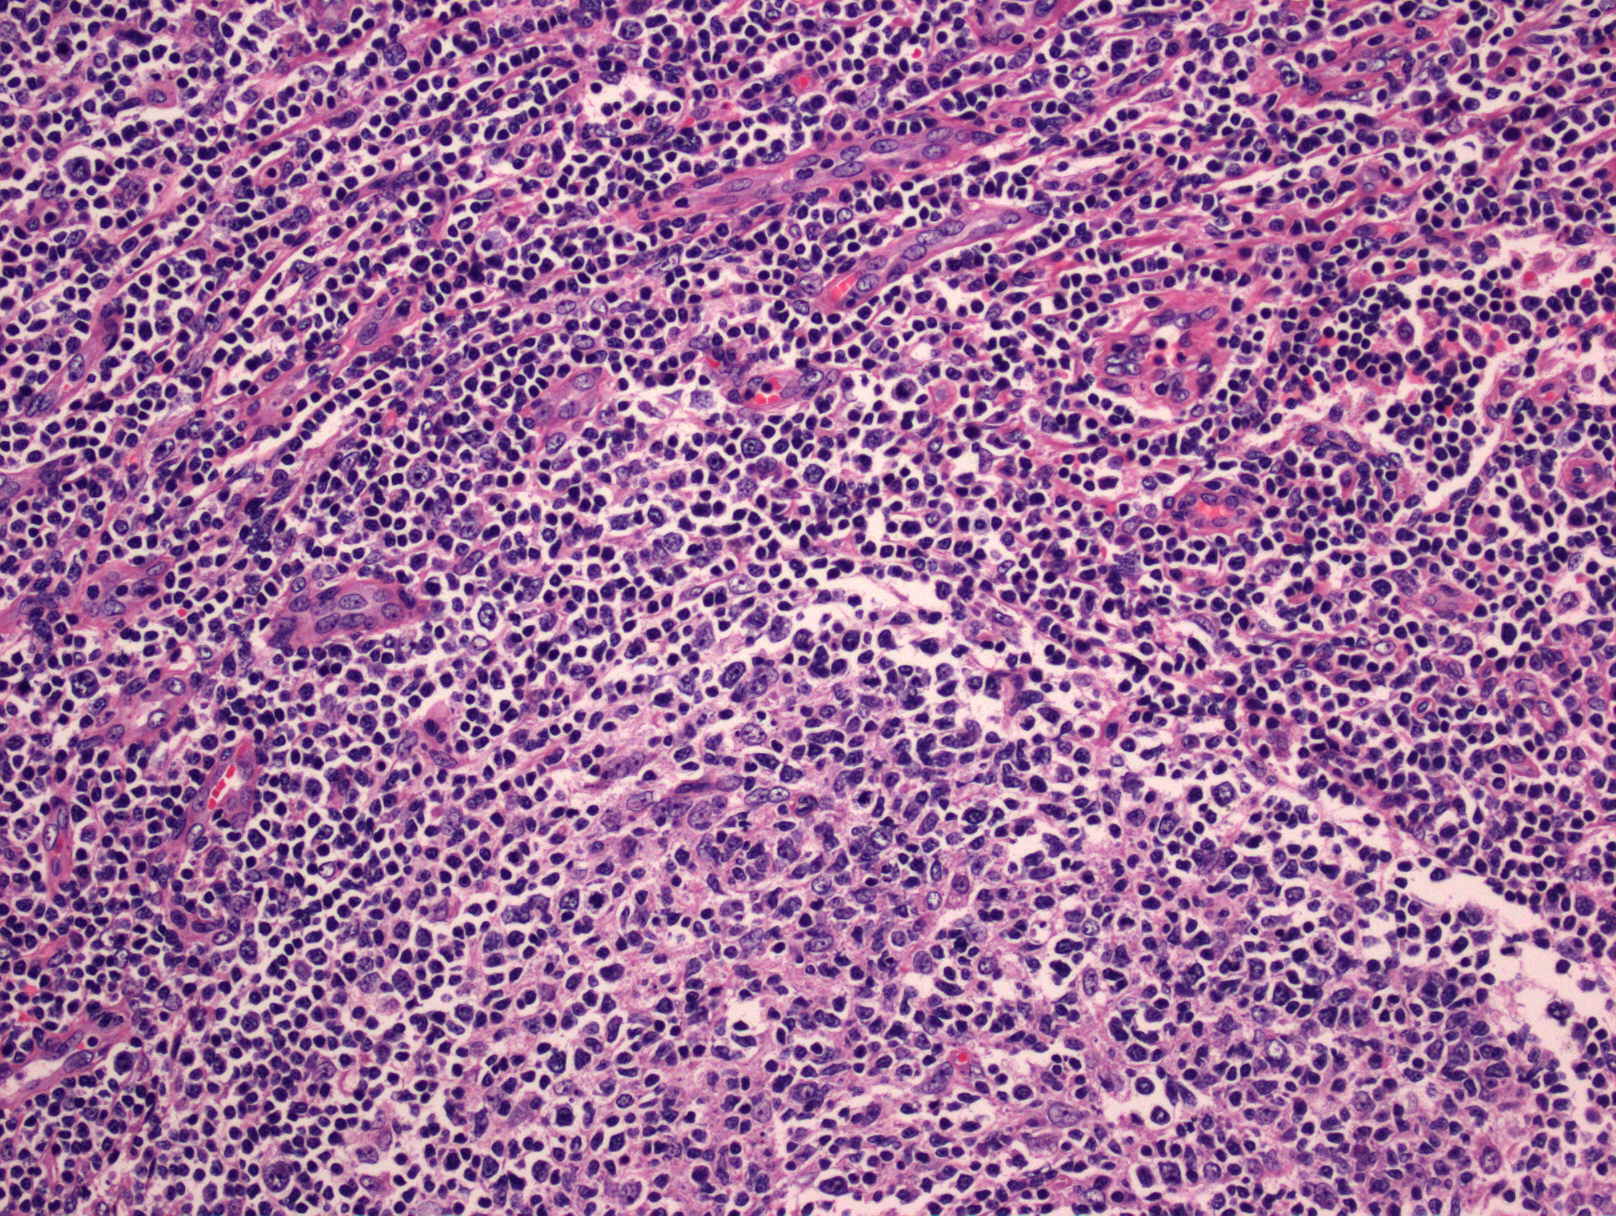

- 肿瘤细胞沿边缘区或滤泡间增生,导致边缘区或滤泡间扩张,可见残存滤泡;或更广泛弥漫浸润致淋巴结正常结构不复存在。

- 肿瘤细胞形态多样,呈单核样、中心细胞样和浆细胞样,并总是混有散在的转化细胞或淋巴母样/免疫母样细胞。时转化细胞数甚至超过 20%,但其中混有小淋巴细胞,且多见于植入的滤泡。

- 有时会发生广泛的瘤细胞滤泡内“植入”, 形态上易与滤泡淋巴瘤混淆。